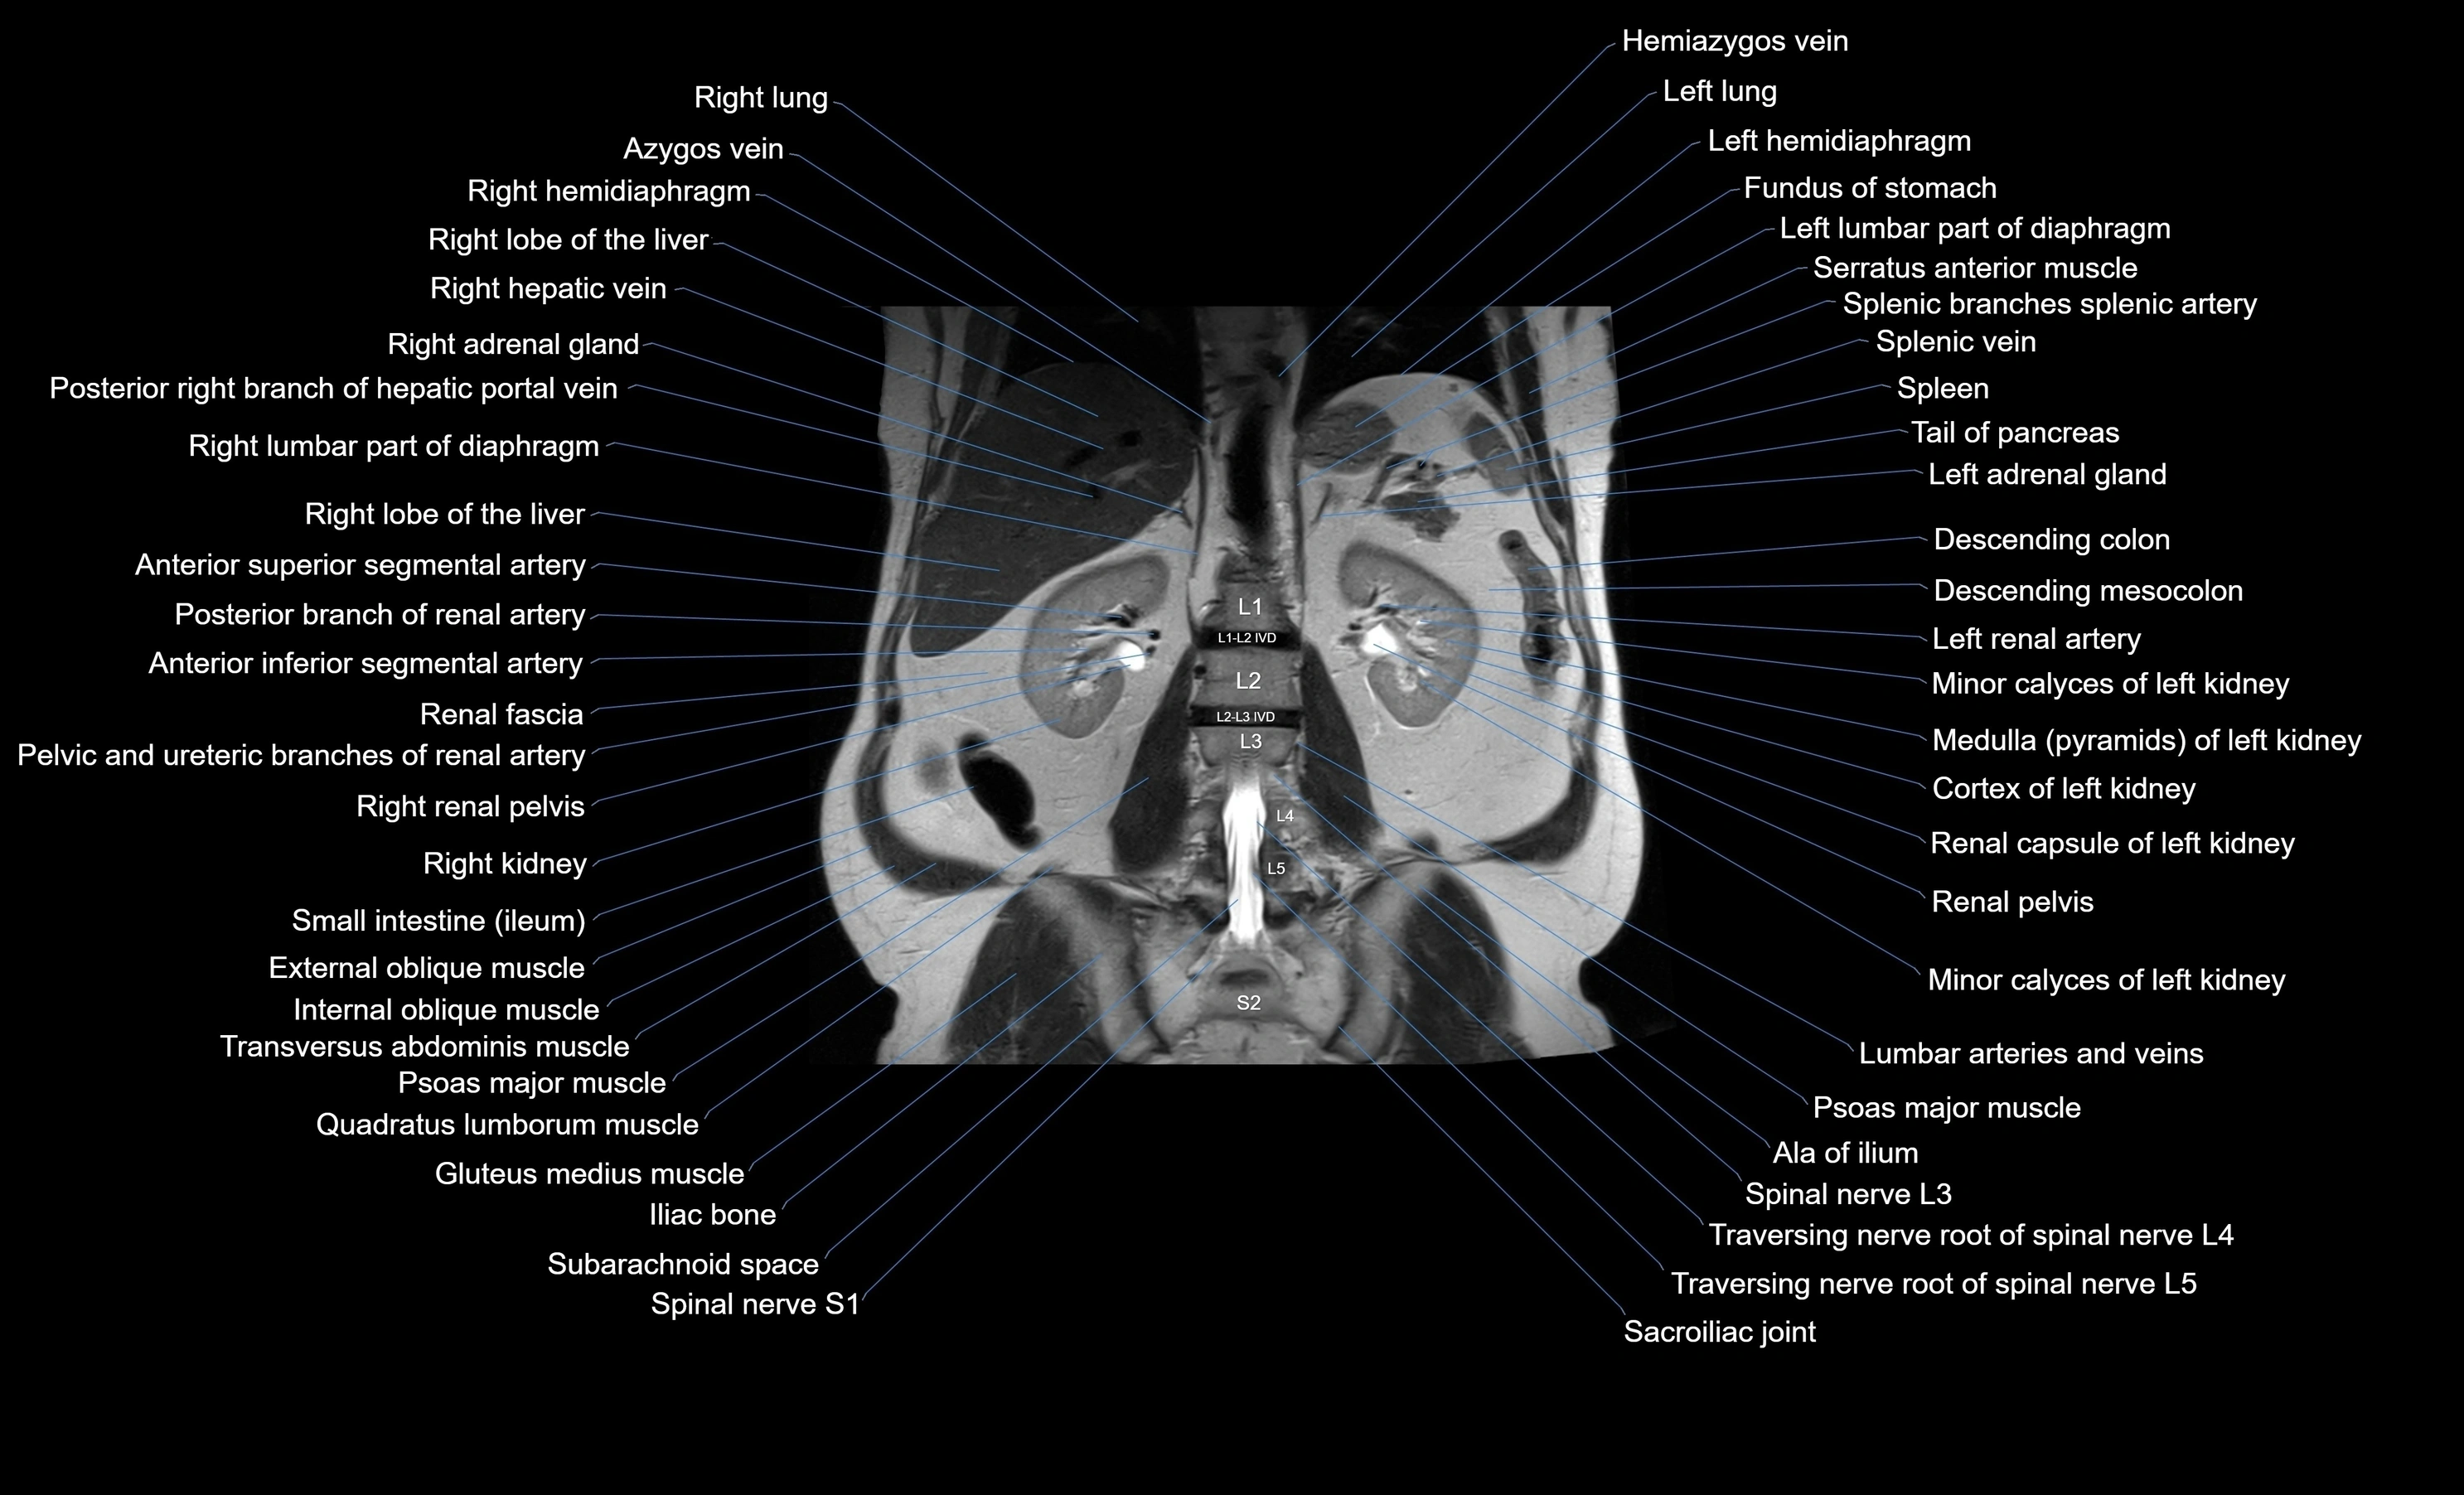

MRI images